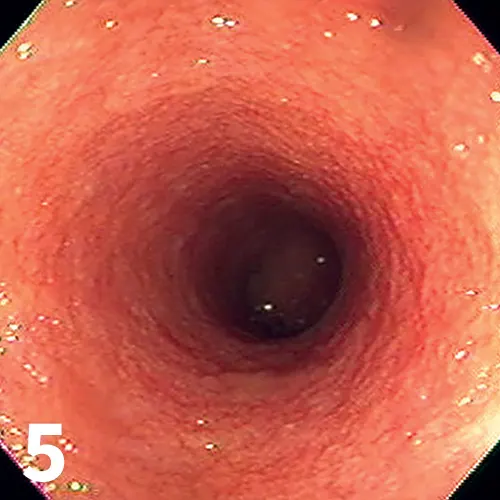

Figure 3

Ultrasound highlighting several features of pancreatitis, including an enlarged pancreas with a hypoechoic parenchyma and hyperechoic surrounding mesentery, as well as a dilated pancreatic duct (arrow). These features are believed to represent acute pancreatitis.

• Abdominal ultrasound (Figure 3) may show ≥3 of the following features: evidence of pancreatomegaly, hypoechoic parenchyma, hyperechoic surrounding mesentery, irregular pancreatic border, dilation of pancreatic or bile ducts, dilation of the cystic duct, abdominal effusion

• A normal-appearing pancreas does not rule out pancreatitis

• Repeat abdominal ultrasound should be considered in light of pancreatitis being a dynamic disease process